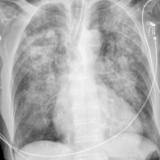

Heart failure

Album: Heart failure

Date: 11/05/2005

Size: 24 items

Views: 45881